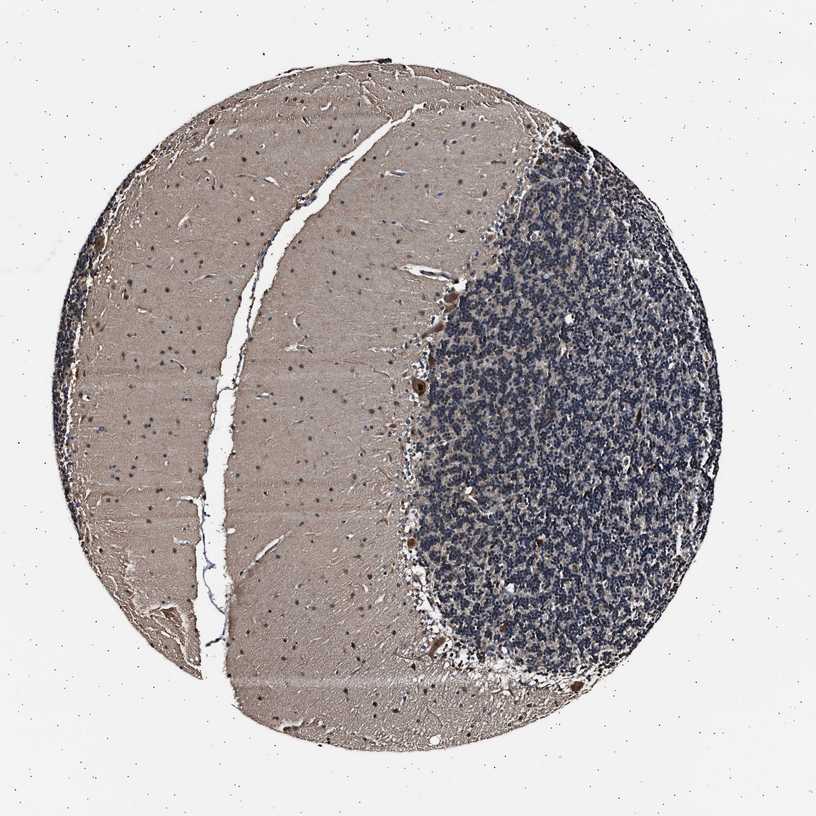

CEREBELLUM - Antibody stainingi

Antibody staining in the annotated cell types in the current human tissue is reported as not detected, low, medium, or high, based on conventional immunohistochemistry profiling in selected tissues. This score is based on the combination of the staining intensity and fraction of stained cells.

Each image is clickable and will lead to virtual microscopy that enables deeper exploration of all samples and also displays staining intensity scores, fraction scores and subcellular localization as well as patient and tissue information for each sample.

Antibody HPA018520Antibody HPA021051Antibody HPA029426

Purkinje cells MediumHighMedium

Cells in granular layer MediumLowLow

Cells in molecular layer LowHighMedium